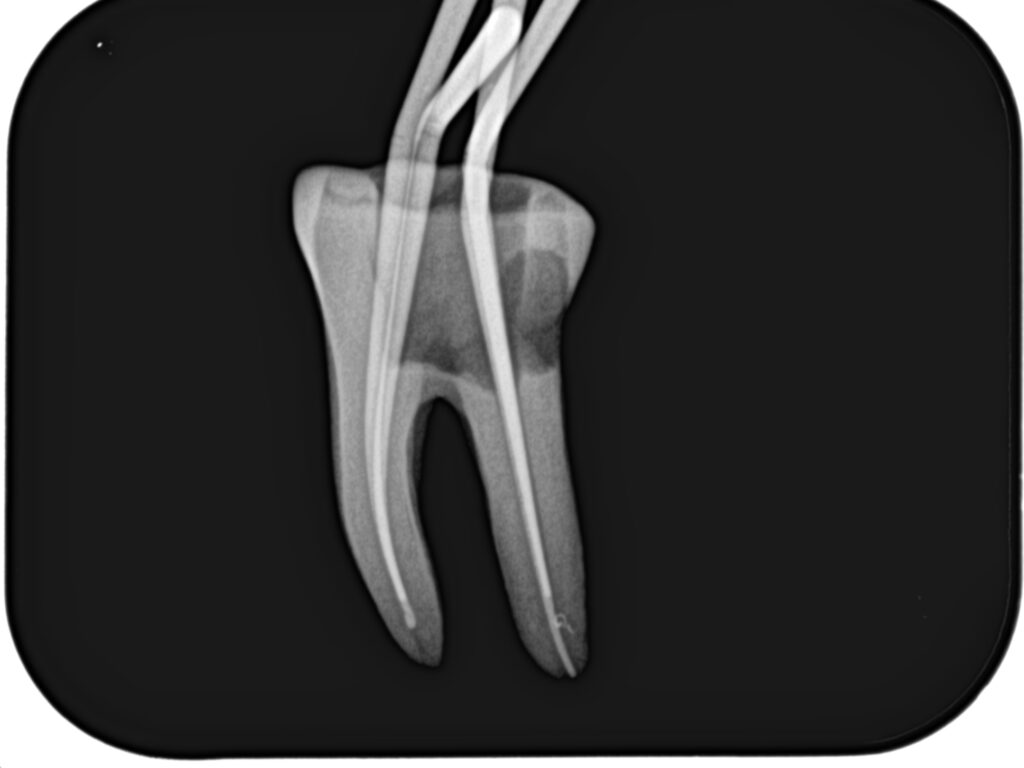

まず作業長の測定方法を行うまでを解説した。

その後、根管形成である。

根管形成が終了すれば、根管充填だ。

日曜日は実習を行った。

土曜日の内容を投影した実習であった。

2本の歯牙で実習し、あっという間に1日は終了した。